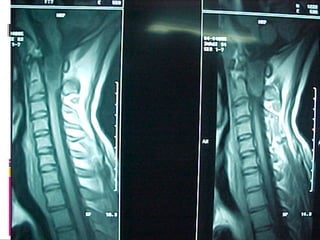

Diagnosis

 MRI

Introduction  15% ofprimary CNS tumors  Cranial:Spinal astrocytoma = 10:1  Cranial: Spinal ependymoma = 3 ~20:1  Most primary spinal tumors are benign  Compression symptoms

• 41.

Types of SpinalTumors  Extradural: (55%)  Intradural Extramedullary: (40%)  Meningioma & neurofibroma  Intramedullary: (5%)